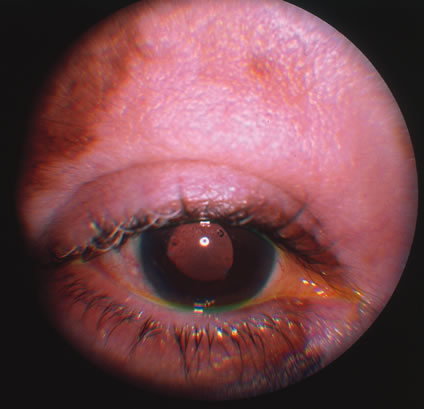

In primary ocular HSV infections, a severe follicular conjunctivitis with regional adenopathy is present. Vesicles may appear on the eyelid skin or lid margin, producing blepharitis (Fig. 3). Corneal involvement initially takes the form of a superficial punctate keratitis, which may progress to dendritic or geographic ulceration. Stromal infiltrates and uveitis are less common and relatively mild in primary disease. In uncomplicated cases, lesions usually heal completely in 2 to 3 weeks without scarring. Most cases of ocular HSV are recurrences. Recrudescent ocular herpes may take the form of dendritic or geographic ulcers, recurrent erosions, interstitial or disciform stromal keratitis, and anterior uveitis.3 HSV may also be an agent of retinitis and acute retinal necrosis (Fig. 4).